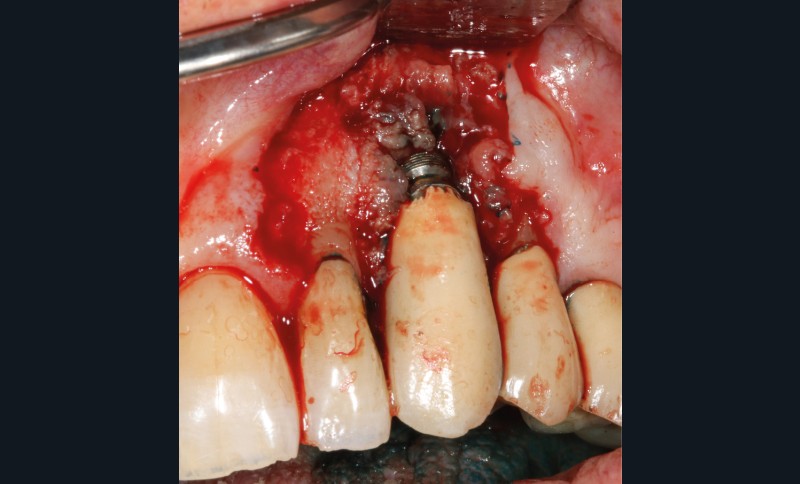

– Le laser Er-YAG, utilisé pour le nettoyage, est un laser avec un milieu actif composé d’yttrium, d’aluminium et de grenat dopé à l’erbium. Avec une longueur d’onde de 2 940 nm situé dans l’infrarouge, le laser Er-YAG est un laser à haute énergie, dont la lumière est absorbée dans l’eau et dans l’hydroxyapatite et qui ne pénètre pas profondément. Ceci permet de couper des tissus mous et des tissus durs, mais également de désorganiser le biofilm bactérie.

C’est un laser idéal pour le traitement chirurgical des péri-implantites. Il permet l’élimination du tissu de granulation à la surface de l’implant et de l’os ainsi qu’une décontamination mécanique par effet photoablatif.– Le laser Diode, utilisé pour la décontamination…